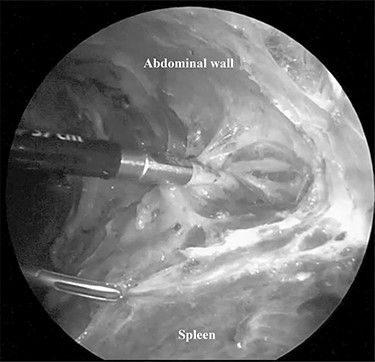

The patient was placed in the right lateral decubitus position. The standing positions of the surgeon and the assistant were on the right or left of the patient depending on the surgical site. Initially, a 12-mm port was introduced through the lateral margin of the left rectus abdominis muscle at the level of the umbilicus. After establishment of pneumoperitoneum with an intra-abdominal pressure of 10 mmHg, two 3-mm ports were inserted in the left upper quadrant at the subxiphoid and left subcostal margin along the mid-axillary line. The accessory spleen was carefully explored through the abdomen. The spleen was mobilized from the lower to upper direction. The initial dissection involved release of the lower pole of the spleen with dissection of the splenocolic ligament, and the spleen was freed from the splenorenal ligament toward the posterior aspect of the splenic hilus using laparoscopic coagulating shears under the guidance of a 3.3-mm needlescope (Karl Storz SE & Co. KG) (Fig. 2). Subsequently, short gastric vessels (Fig. 3) were divided, and the upper pole of the spleen was mobilized with the division of the splenophrenic ligament. Then, the splenic hilus was divided using a linear stapler (Fig. 4). The isolated spleen was then placed in an impermeable bag (Endo-Catch II; Covidien Co. Ltd.) and extracted via a 12-mm port after morcellation using the placenta forceps without extending the initial 12-mm incision (Fig. 5). After irrigation with normal saline and confirmation of hemostasis around the resected area without inserting a suction drain, only the 12-mm port site was only closed, and the 3-mm port sites were left open.

LS was generally performed using a four-port technique for NS as well. We performed NS using a three-port technique. To complete our technique, several skills including the intra-operative position of the patient to manipulate the spleen easily, mastering the technique that requires the use of both hands, and extraction of the spleen after morcellation using placenta forceps so as not to extend the initial 12-mm port site are necessary. The right lateral decubitus position tilts the spleen inward to divide the lateral side of the spleen. The technique using both hands provides an operative field similar to that created using the forceps of the assistant. Morcellation of the spleen using the placenta forceps prevents perforation of the impermeable bag due to its round shape. Not extending the 12-mm port incision as seen in Fig. 4 provides a better cosmetic outcome. There were no post-operative complications and there was no need to insert the suction drain. Confirmation of secure hemostasis during the surgery can achieve those outcomes.